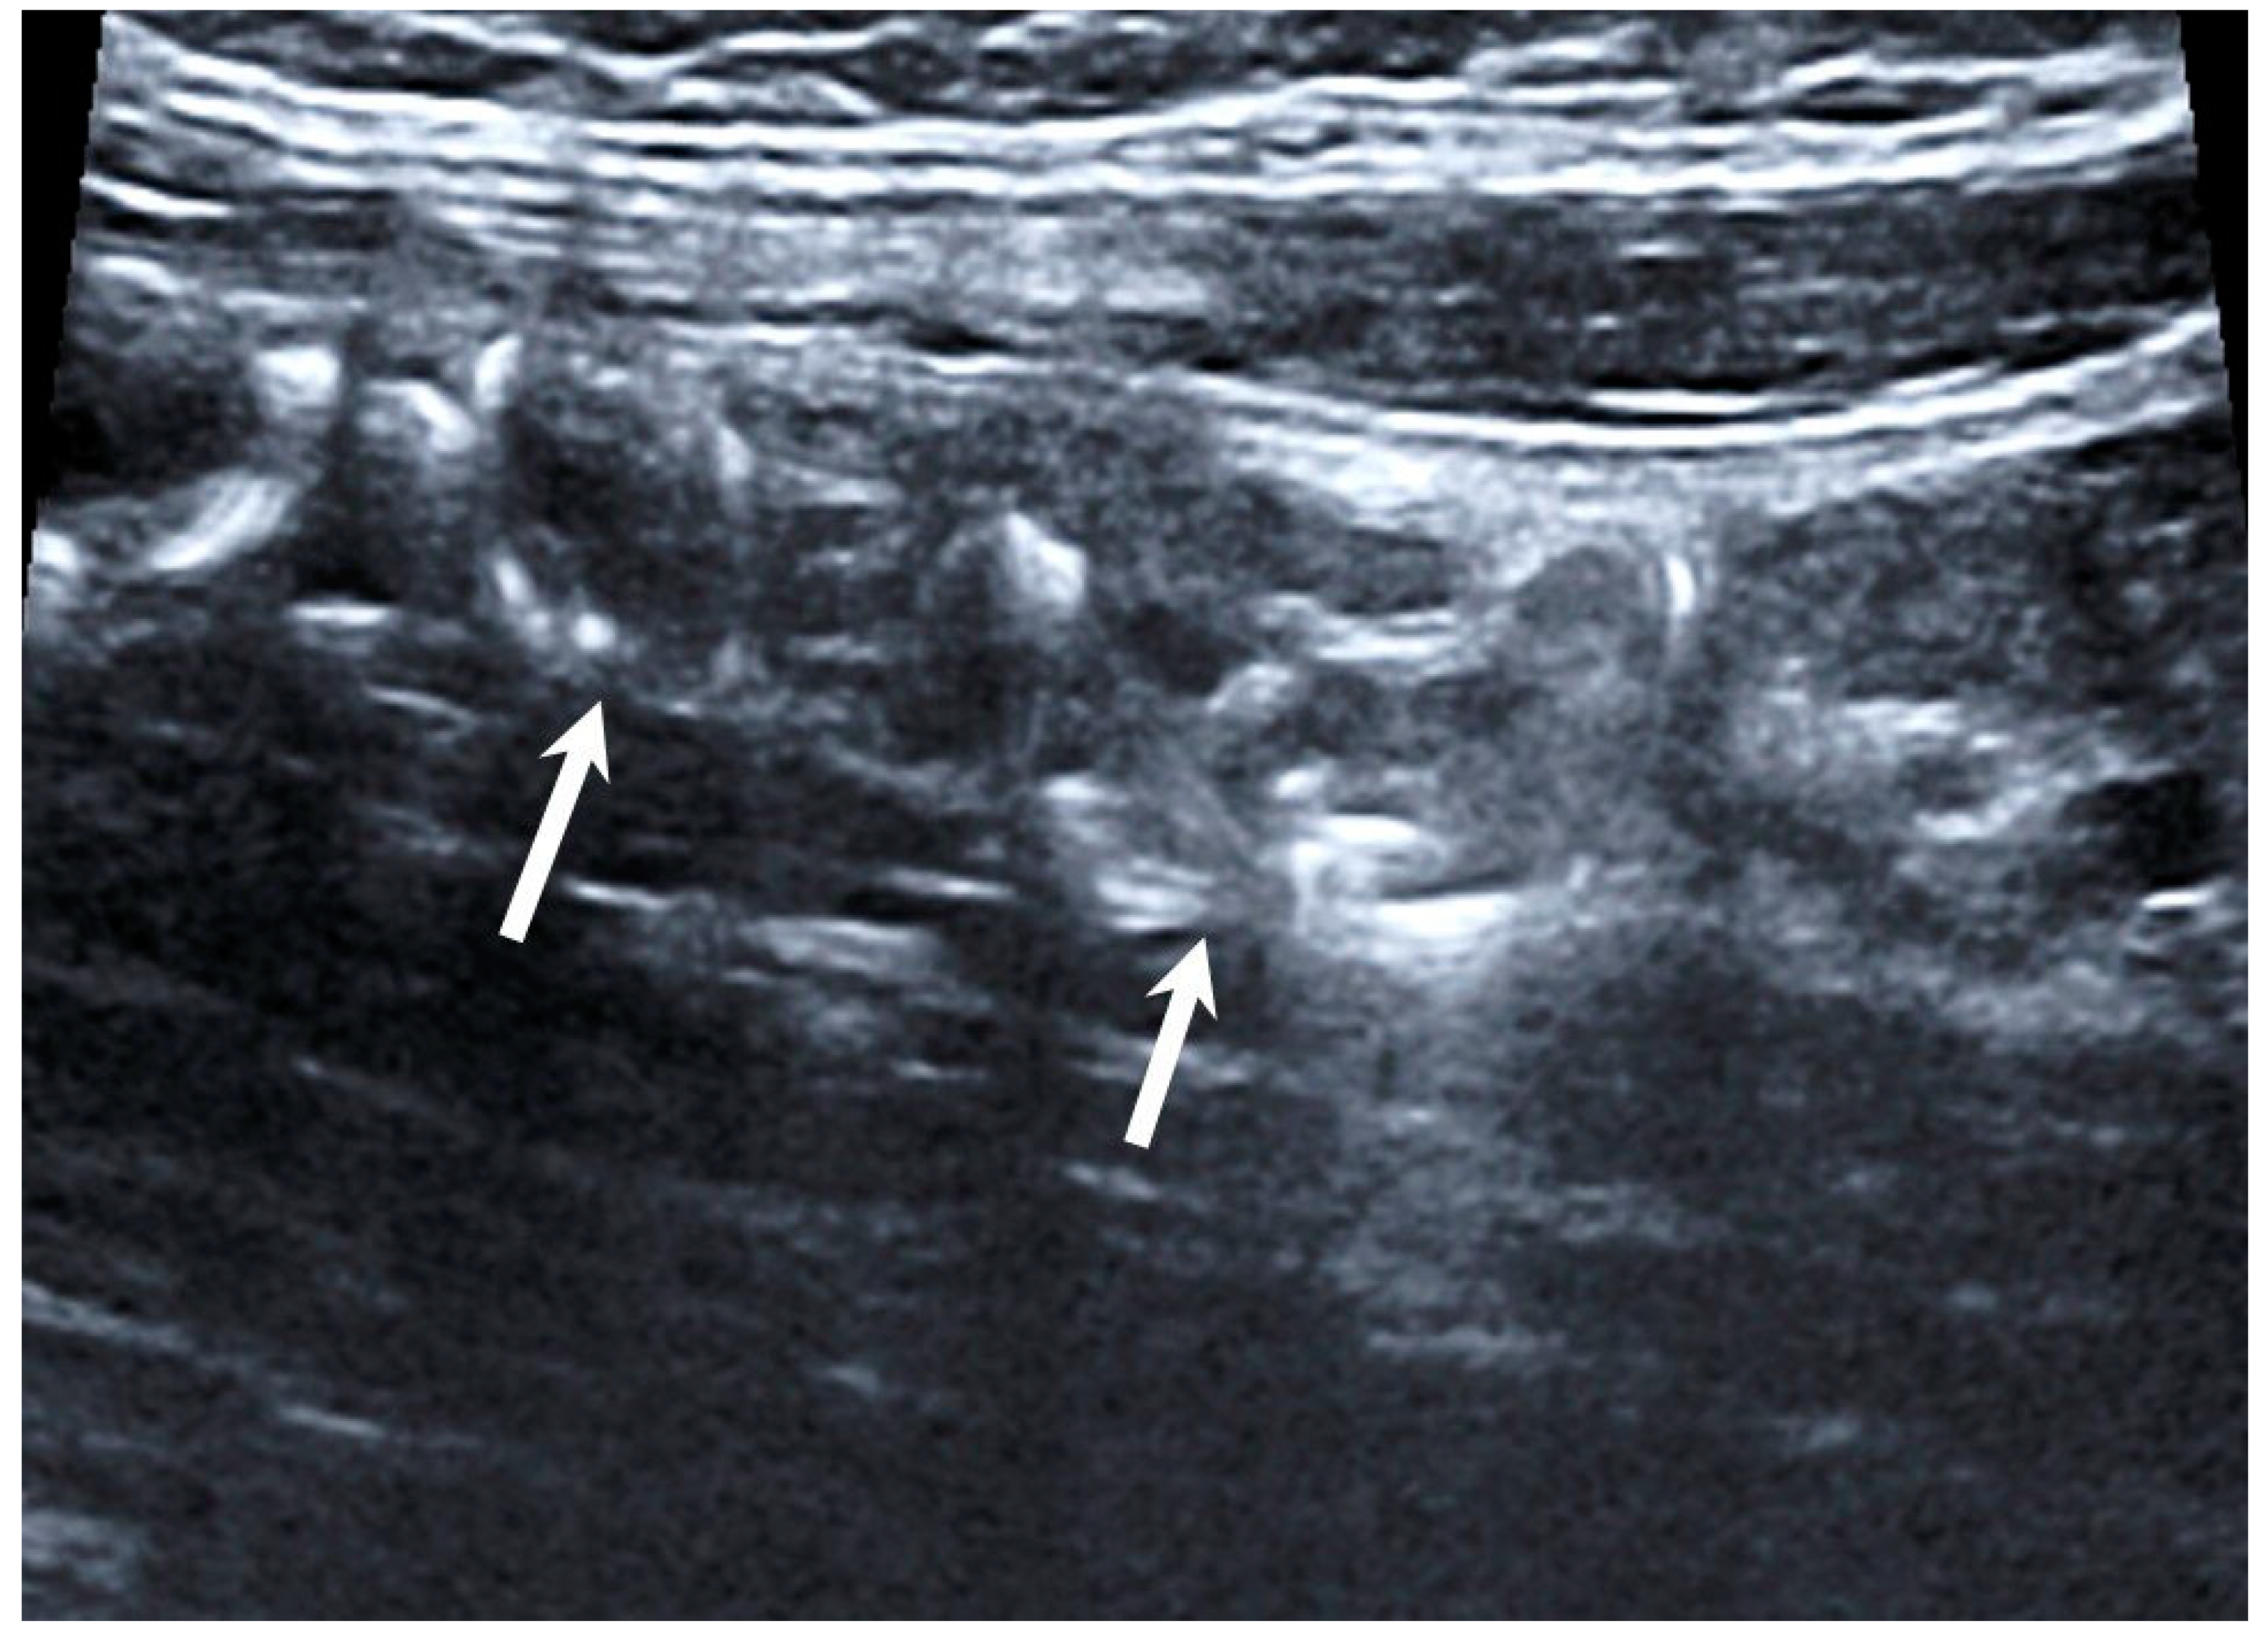

Technical success of EEGV, i.e., elimination of gonadal veins reflux, was achieved in 100% of patients. No complications were observed during the intervention. According to TVDUS, all 70 patients had no blood flow through the occluded gonadal vein segments (Figure 2).

Figure 2. Duplex ultrasound scanning. Hyperechoic structures (coils) in the lumen of the gonadal vein (arrows).